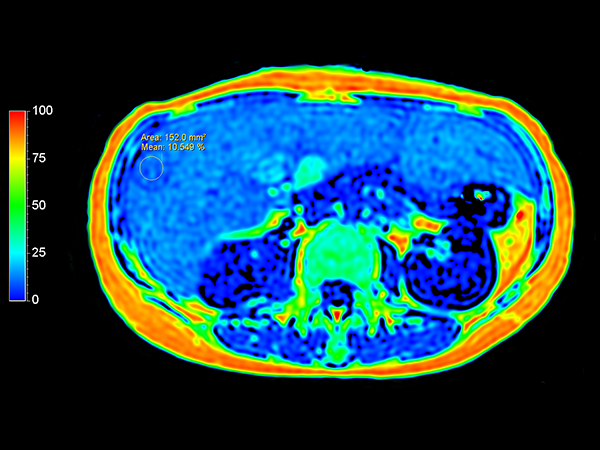

Previous MR in this patient has shown a large liver with fatty spots and signs of general steatosis. With mDIXON Quant an average fat fraction of 16% and peak at fraction of approximately 22% is found, see the images with ROIs of 12% and 20% fat fraction. The diagnosis is steatosis hepatis magno gradu and ocal/segmental steatosis. mDIXON Quant provides a quantitative estimation of the fat fraction in the liver in only 1 breath hold.

mDIXON Quant (fat fraction map)